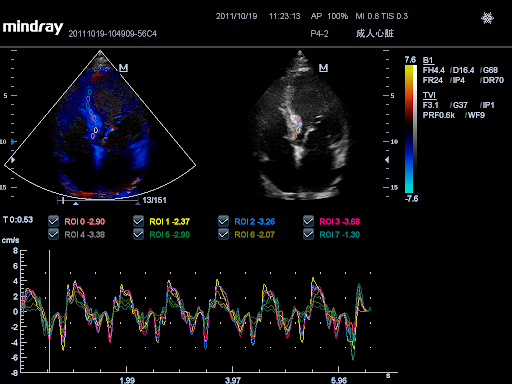

TDI с QA

Тканевая допплеровская визуализация позволяет количественно оценить локальное движение и функцию миокарда, предоставляя полные режимы TDI для более быстрой и прямой диагностики.